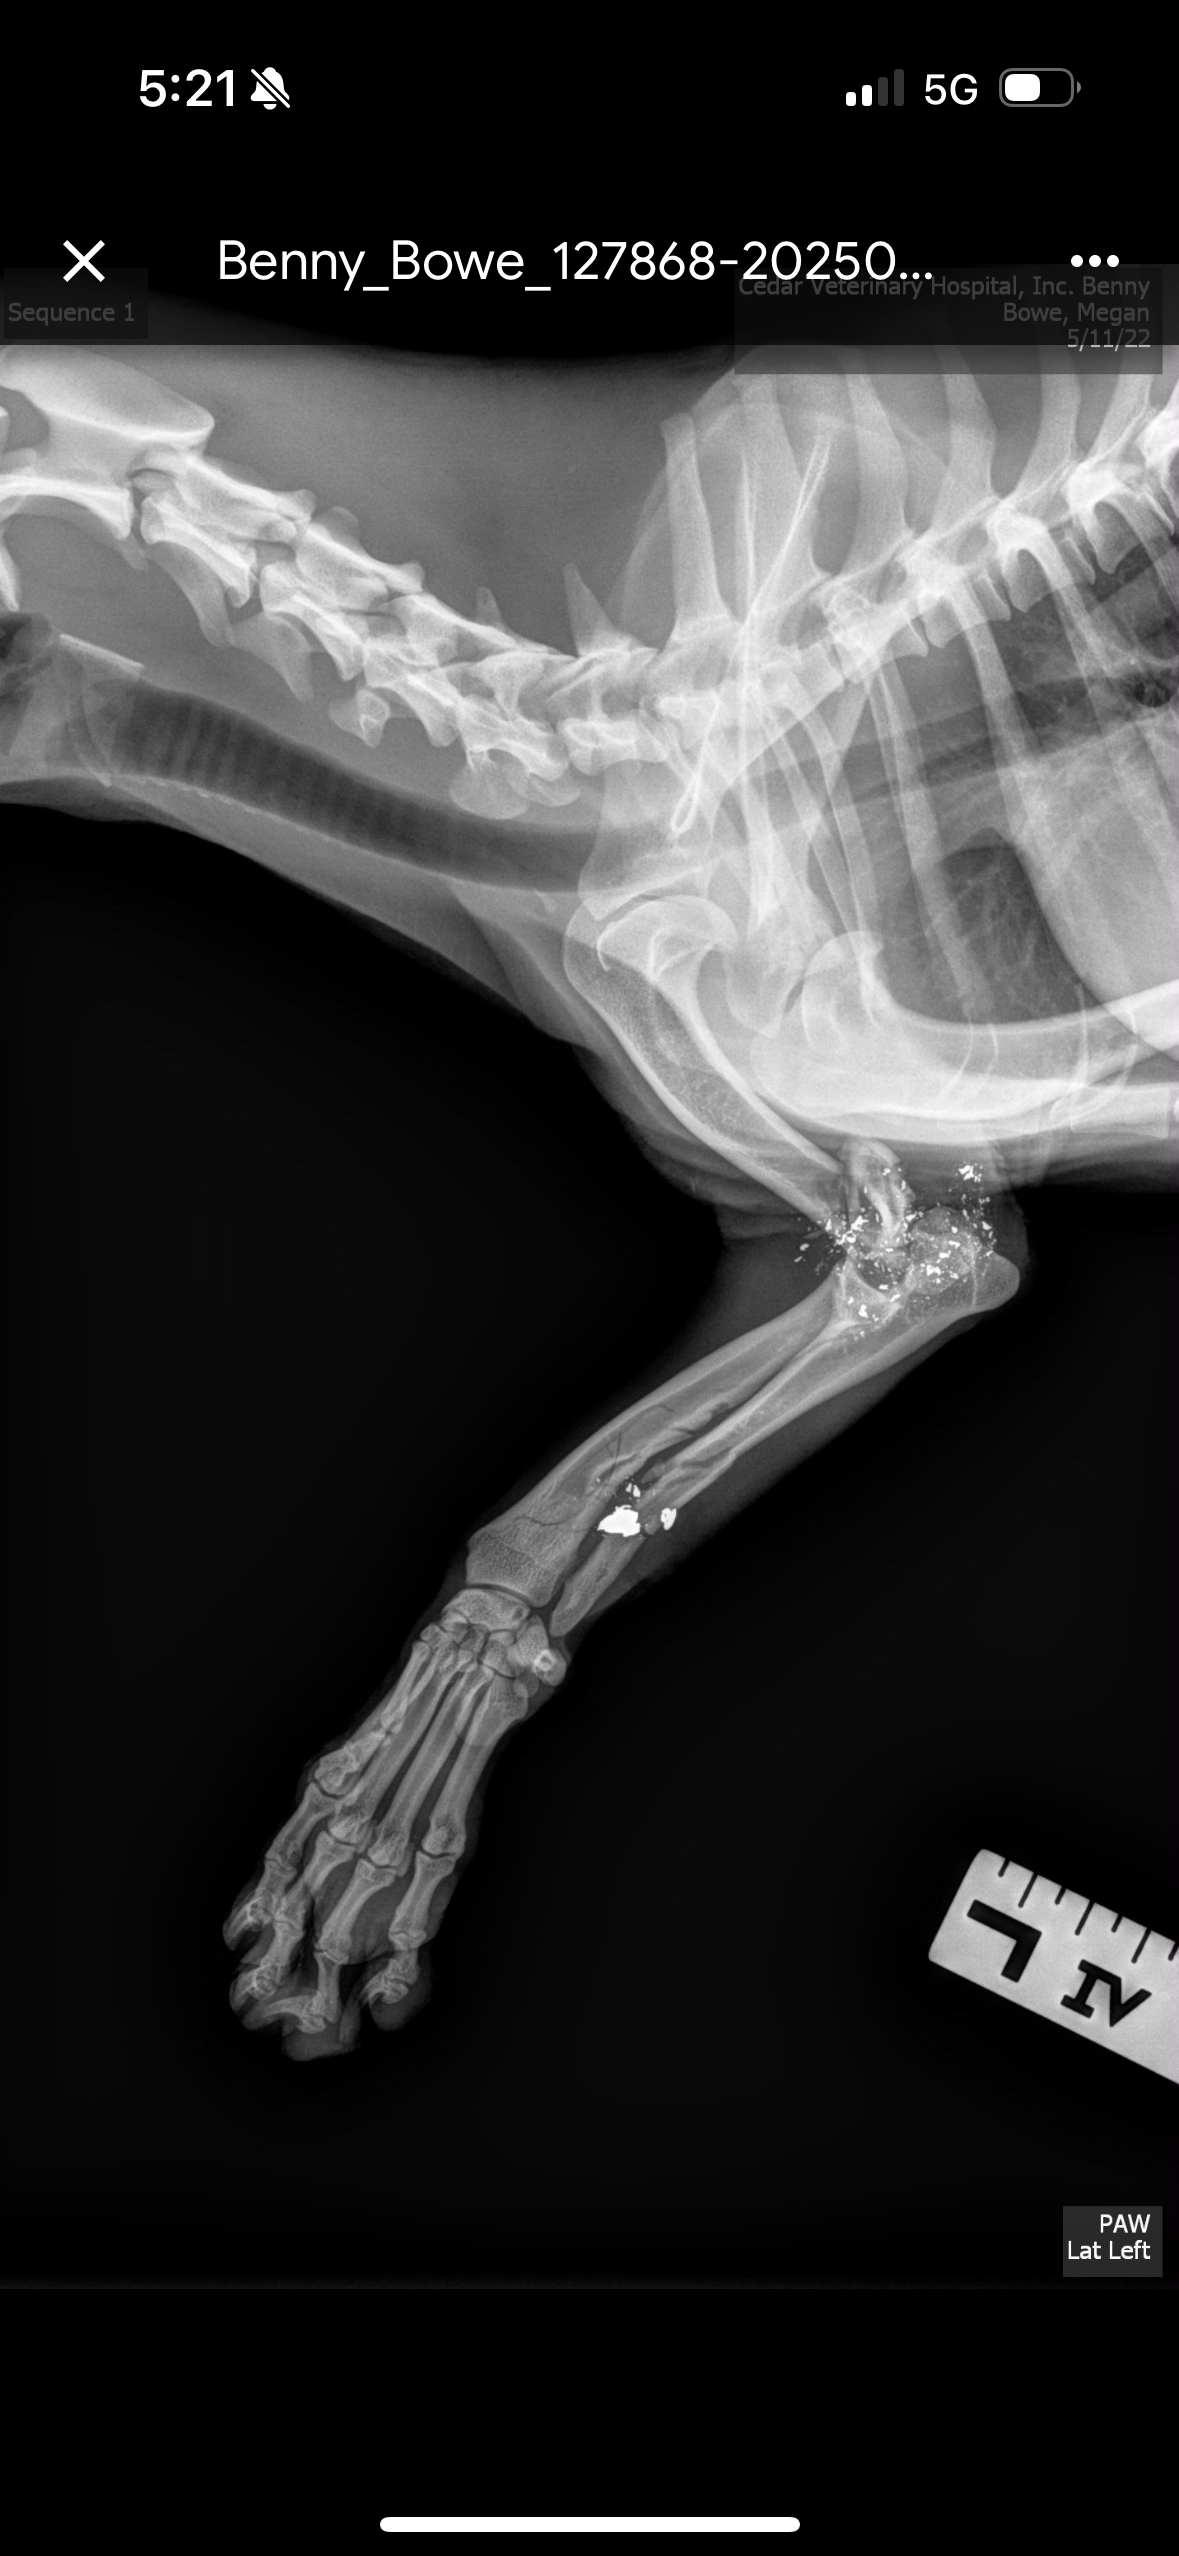

Benny was cruelly shot multiple times and left to die in an orchard south of Avenue 12 in late April. Both his front legs were broken, and his back foot was broken. He could no longer walk, but somehow he fought, crawled, and survived until help arrived. He was in excruciating pain, too weak to cry out or defend himself. Warning: The photos, x-rays, and videos are disturbing.

We rushed him to emergency care, where he was stabilized, treated for shock, and given fluids. He’s now receiving regular vet visits, bandage changes, and preparing for a critical procedure to remove bullet fragments and possibly insert pins to stabilize one of his legs. The other front leg may still require amputation if it doesn’t heal.